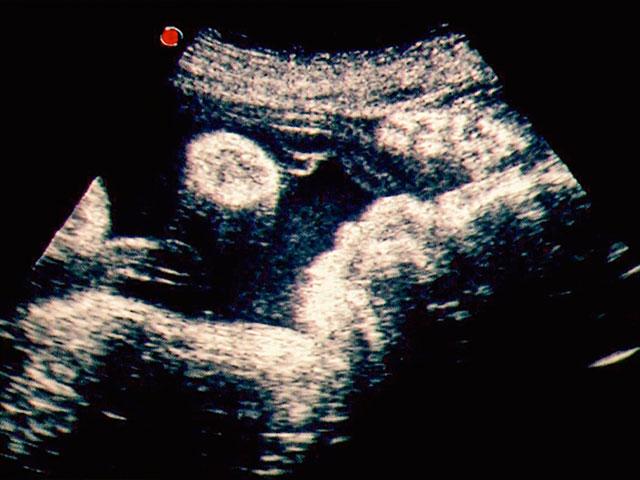

An unborn baby with a deadly tumor was taken out of its mother's womb for surgery, then placed back into the womb to continue growing.